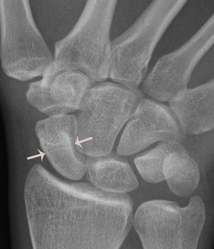

Unfortunately scaphoid fractures do not always show on an initial xray; they may not show up until the initial pain has settled down. The following patient's fracture did not show up on the original xrays taken in the A&E department. An MR scan shows the fracture clearly; the blue arrow points to the white area in the scaphoid that represents bruising in the bone. The subsequent xray confrims the presence of the fracture, albeit still very subtly (white arrows).

The above xrays show a scaphoid waist fracture (indicated by the red arrow) before fixation and showing solid union after screw fixation.